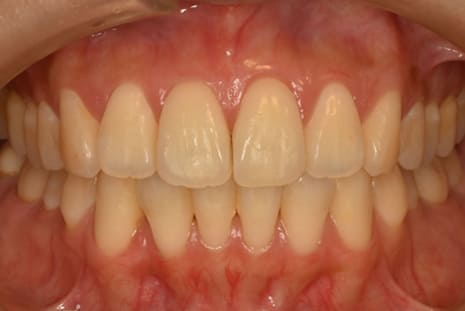

マウスピース矯正装置にて上下顎の矯正を行いました。

足りないスペースは側方への歯列拡大とIPR(歯の間の削り込み)を行い矯正しました。